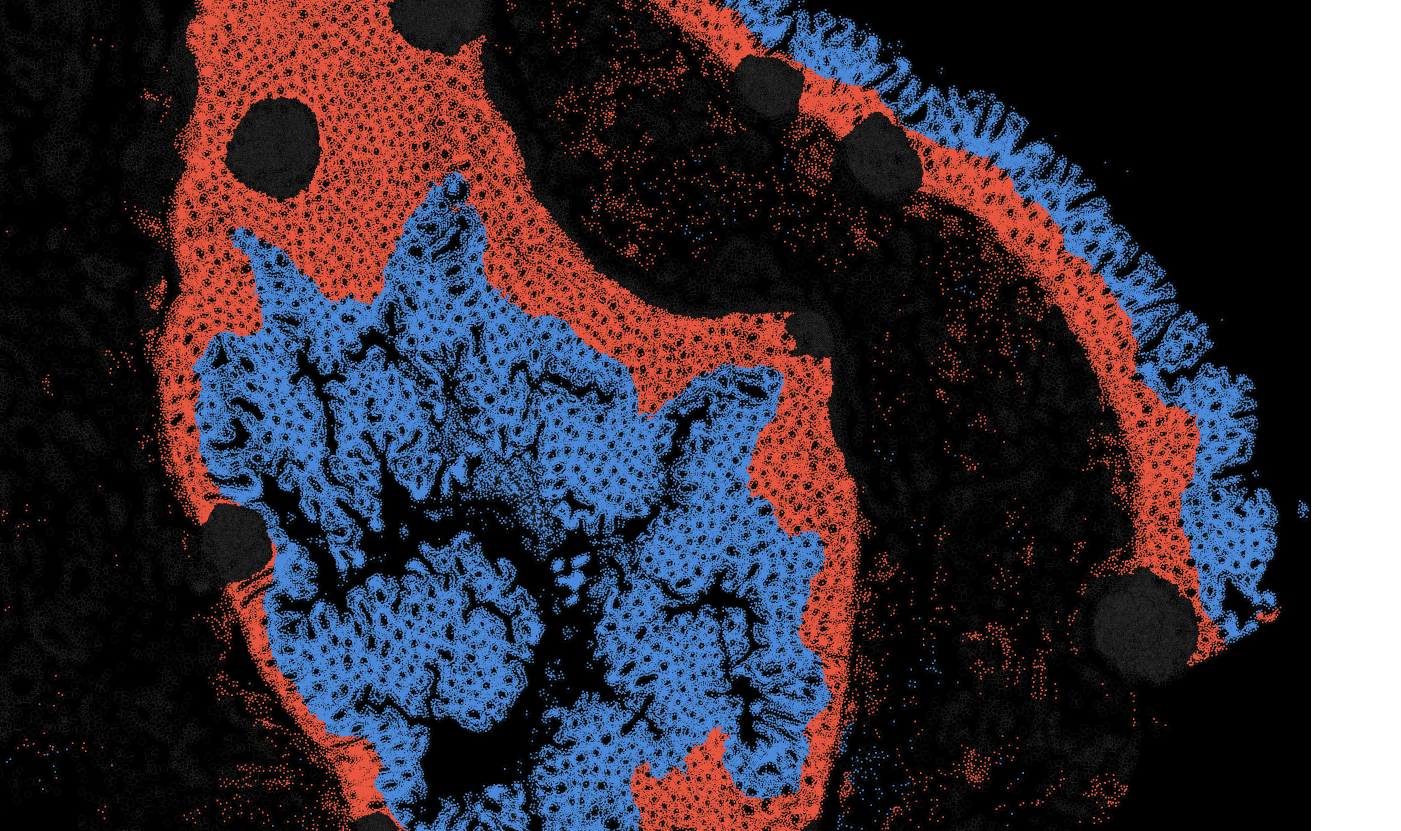

Applicability across different spatial resolutions

The segmentation module is designed to help researchers explore tissue architecture at multiple levels of detail, depending on their scientific question. Users can begin by dividing the tissue into major anatomical structures to gain a broad overview of the spatial landscape. From there, they can zoom into a specific region of interest and further segment it into sub-tissue compartments, enabling more refined analysis of microenvironments and localized biological processes.